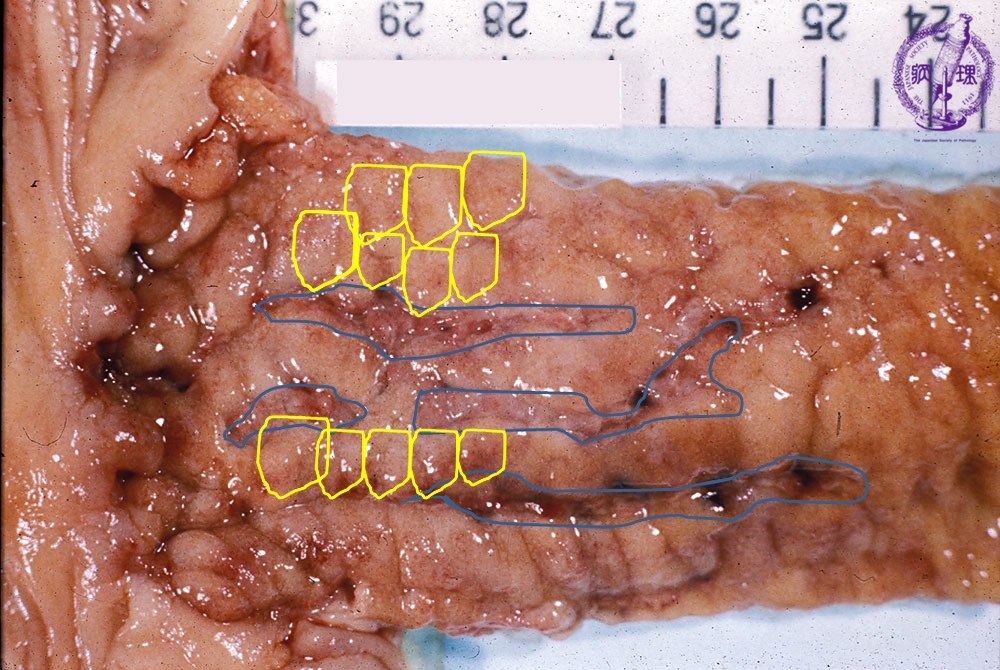

- ★(3)Crohn’s disease

Gross appearance: Linear ulcers (blue) and a cobblestone appearance (yellow) are distinctly seen.